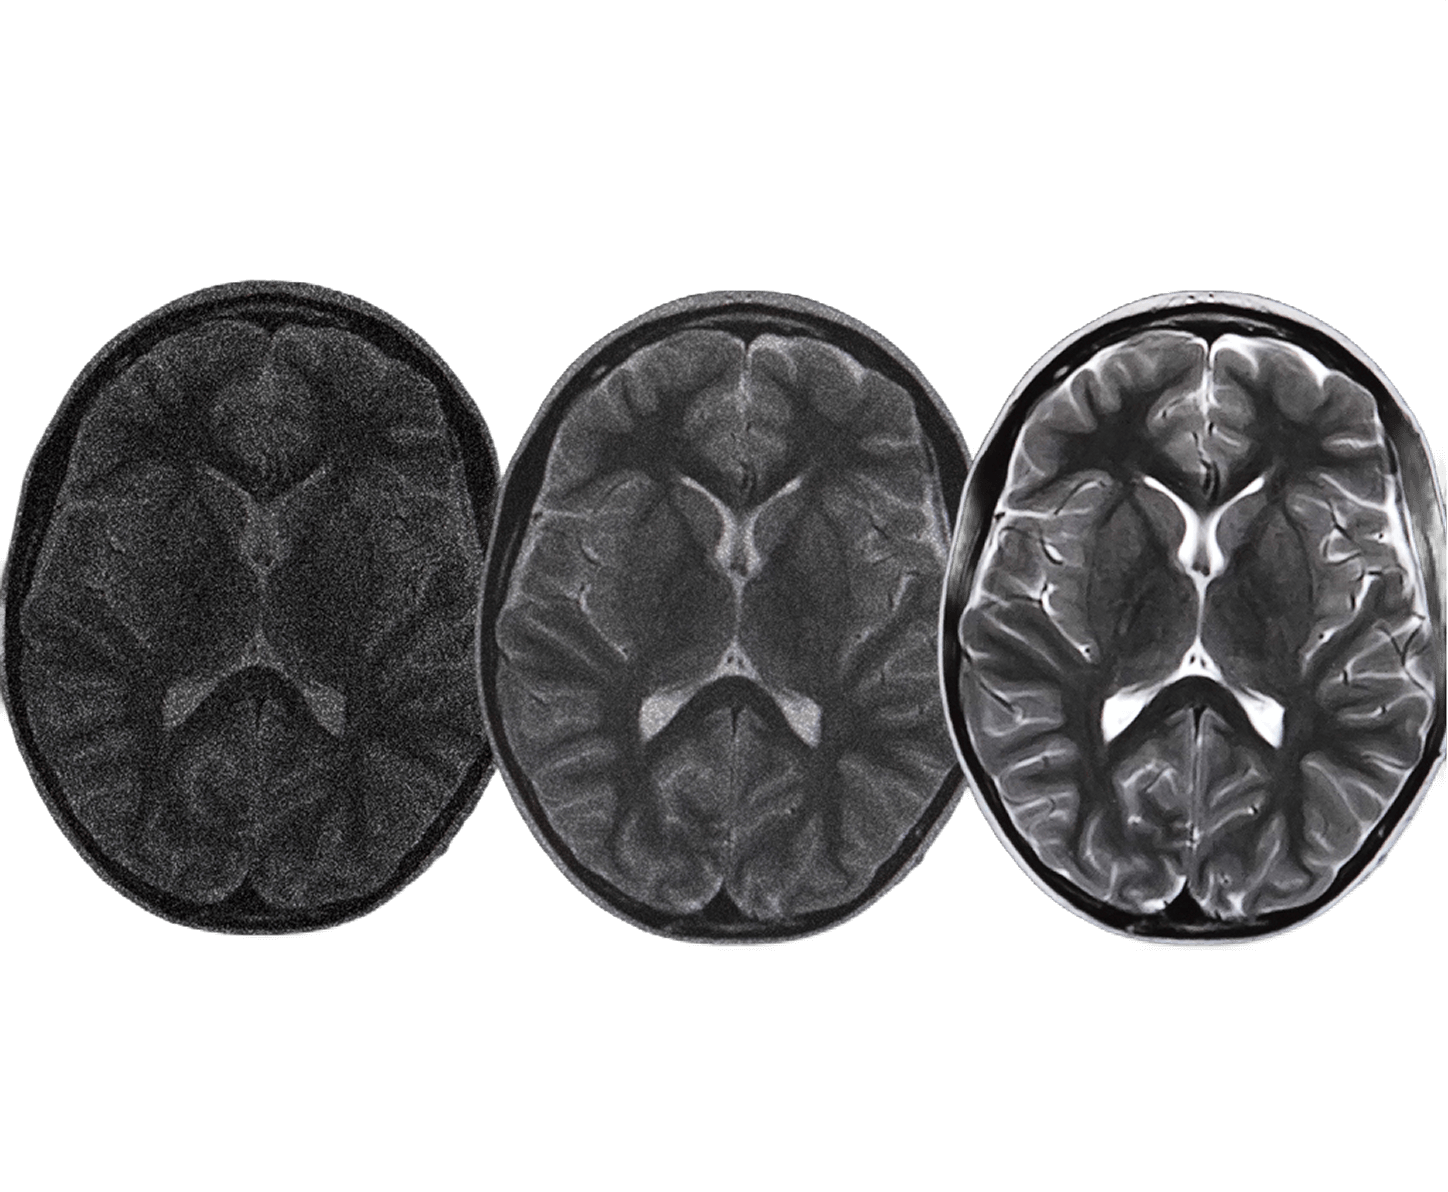

Thoughtful scan design behind every image

Each scan follows proprietary imaging sequences specifically for our screening approach, helping produce consistent views across organs, tissue, and structures throughout the body.